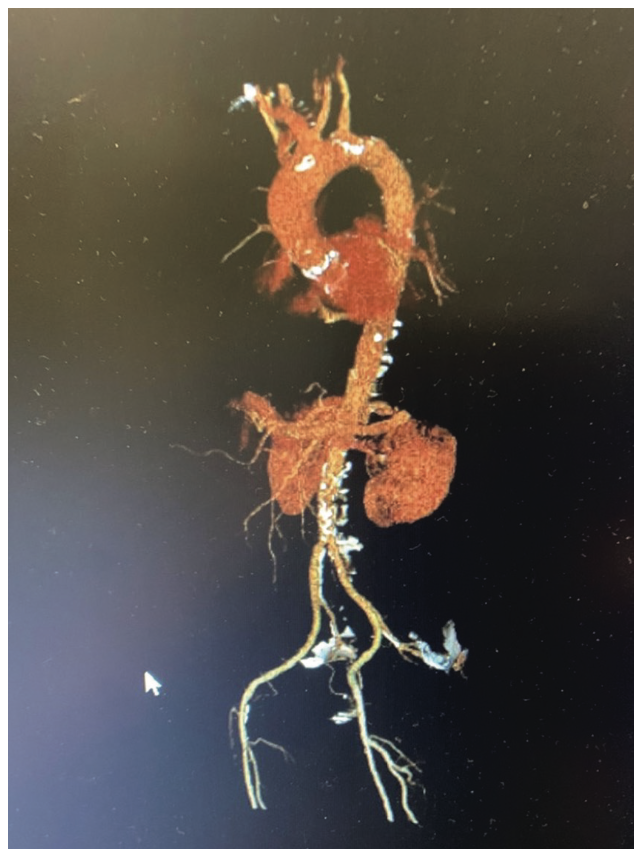

As transcatheter aortic valve replacement has become a frontline treatment for aortic valve stenosis (AS), CT has become the cornerstone imaging modality for the pre-TAVR workup. CT provides 3-dimensional images of the heart, and offers a rapid and complete evaluation of aortic valve morphology and size (Figure 6). CT also evaluates the ascending aorta, coronary arteries, peripheral access vessels, and prognostic factors (Figure 7). Additionally, it provides preprocedural coplanar fluoroscopic angle prediction to obtain complete assessment of the patient. The most relevant dimension in preprocedural planning of TAVR is the aortic annulus, which can determine the choice of prosthesis size.12

Once the location of the aortic root is identified on the unenhanced scan by the CT technologist, the second enhanced scan starts with a 10 mm scan coverage acquired during the initial IV contrast bolus technique, allowing for optimal peak enhancement to the aortic valve. A third scan is initiated, serving as the final portion of the CTA of the chest, abdomen, and pelvis, or whole-body scan. The whole-body CTA evaluates the entire aorta, ilio-femoral arteries, and coronary arteries. The whole-body study guides the physician in obtaining vascular access, as it can visualize the tortuosity of the aorta and the vascular access routes (iliofemoral, subclavian, trans-apical, or direct aorta). CTA is also essential to identify patients with increased anatomical risk for coronary artery occlusion in valve-in-valve (ViV) procedures (Figure 8). CTA is also very useful in the evaluation of late complications, such as perivalvular leaks, thrombosis, and valve displacement.12,13